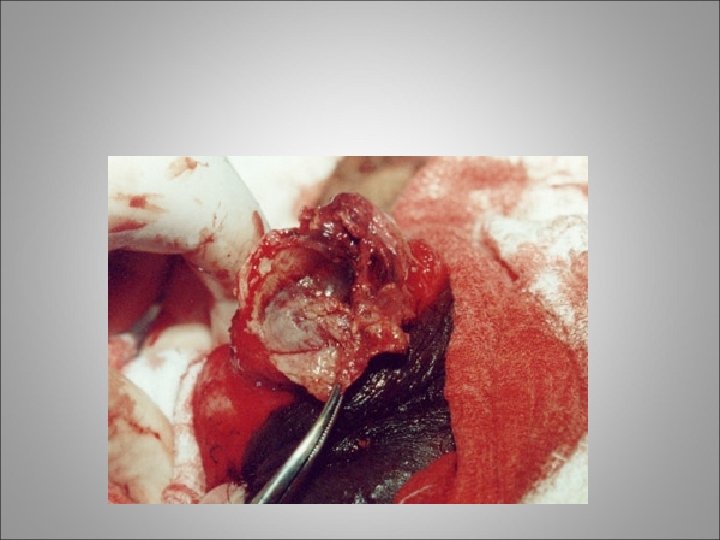

scrotal exploration • Clinical hematoceles that are expanding or of considerable size (eg, 5 cm or larger) should be explored • Collections of smaller size are also often explored, because it has been shown that such practice allows for more optimal pain control and shorter hospital stays • If the testis is fractured, testicular debridement and surgical closure of the tunica albuginea are necessary